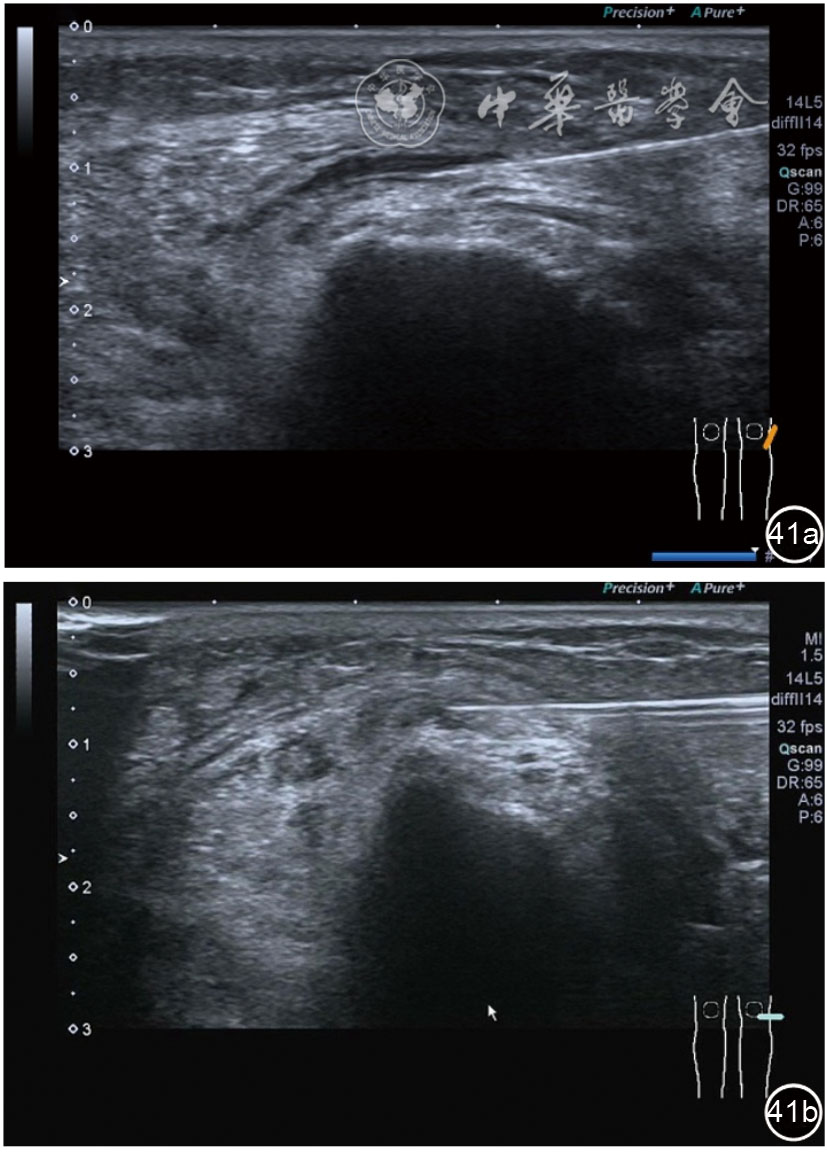

1.关节内表现。(1)骨改变。表现为骨末端或关节周缘出现的骨质局部突起改变,其后方伴或不伴有声影,多见于膝关节内侧缘和外侧缘(图1)。(2)软骨改变。股骨关节面改变可以在长轴及短轴切面显示,嘱患者屈曲膝关节,足平置于检查床,股骨滑车及股骨髁上半部分的关节面即可轻松显示。超声探查可见股骨负重面关节软骨发生不同程度的改变,轻者关节软骨浅侧边界模糊,重者可见关节软骨薄、缺失,软骨下骨缺损改变(图2)。(3)半月板外突。一般内侧半月板突出多见,外侧半月板突出比较少。半月板可见不同程度的外突,同时伴有膝内侧副韧带向外移位(图3)。半月板外周缘性滑脱是指半月板突出超出胫骨平台边缘的距离≥3 mm,其可引起一系列临床症状,早期诊断、早期治疗可以预防骨关节的进一步损伤。(4)交叉韧带损伤。可见前后交叉韧带增粗,回声减低(图4)。(5)髌上囊积液。膝关节是最容易发生积液的关节之一。患者仰卧位,关节积液最常见于膝关节上外侧,因为关节囊向髌股关节上外侧突出。髌上囊积液采用10~18 MHz的高频线阵探头于股四头肌腱纵断面及横断面扫查均可显示,探头频率取决于患者体型。超声可见低回声积液,慢性可伴有丛状滑膜增生(图5)。(6)脂肪垫水肿。脂肪垫在髌骨附着点处回声增强、增厚(图6)。

图5 髌上囊积液、滑膜增生超声图像